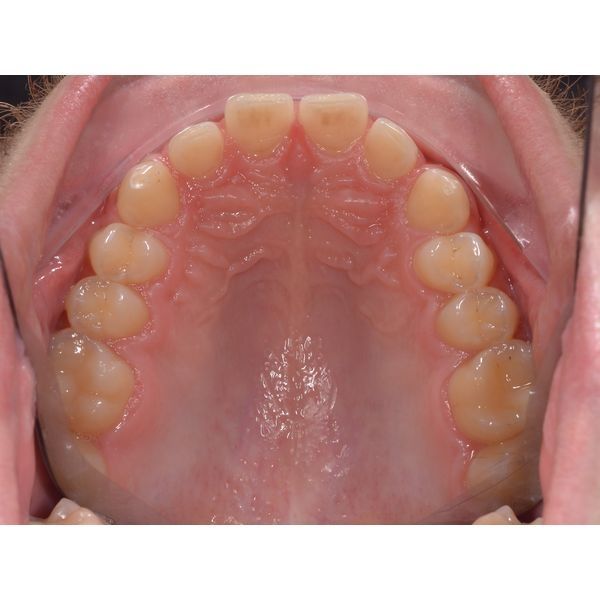

- профицит (избыток) места на верхней челюсти;

- фотопротокол (серию снимков) полости рта и лица;

- расчёт контрольно-диагностических моделей.